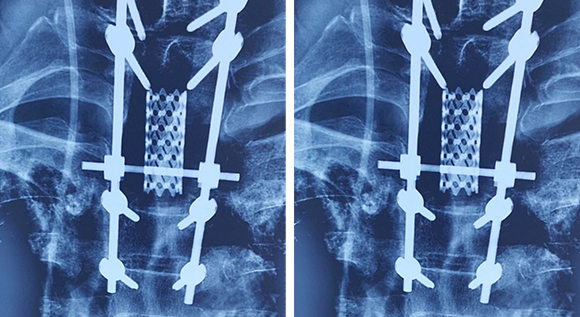

• 2脊柱肿瘤全脊椎切除内固定术